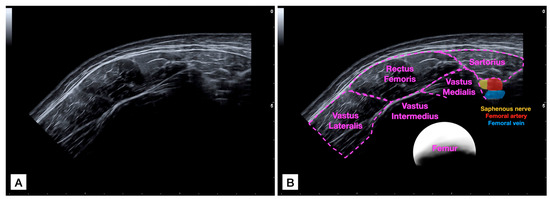

For acquiring the panoramic US image (Figure 1), the probe was placed in the medial and anterior aspect of the thigh at the mid-distance between the patellar base and the anterior inferior iliac spine to locate the sartorius muscle and visualize it in the lateral extreme of the image. Then, the probe was glided laterally (applying the minimum pressure possible) until it completely covered the rectus femoris muscle and the vastus lateralis was partially visualized. Gliding speed was controlled at 5 cm per second to try and apply a uniform light pressure during the path [16]. It was decided to set a constant speed to ensure that each scan is comparable, reducing variability introduced by different scanning speeds. In addition, faster speeds might result in blurred images or missed details, while slower speeds could lead to prolonged examination times without significant improvement in image quality. Both examiners underwent training sessions (practicing this protocol) for 30 min to familiarize themselves with the desired gliding speed.

Figure 1.

Raw panoramic ultrasound (US) imaging acquisition of the rectus femoris muscle (A) and image with identification of structures (B).